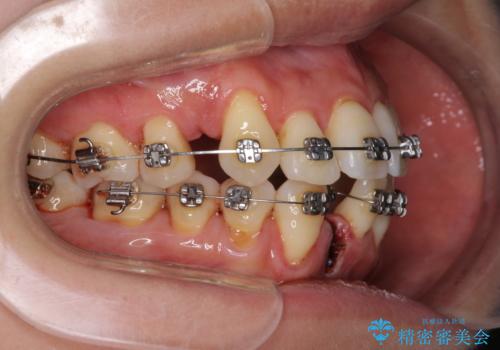

- メタルブラケット

- 上下前歯のでこぼこを気にされ、矯正治療を希望された患者様です。

費用を抑えるため、メタルブラケットを採用し、抜歯矯正を行うこととしました。

通常であれば、上下顎左右小臼歯各1歯の合計4本を抜歯しますが、歯肉退縮の著しい下顎前歯を抜歯して欲しいという患者様の強い希望により、上顎のみ左右小臼歯2歯を、下顎は前歯を1歯を抜歯することとしました。

抜歯する歯を変更したため奥歯の咬合はアンバランスとなりましたが、前歯は綺麗に整い、歯肉退縮も回避できました。